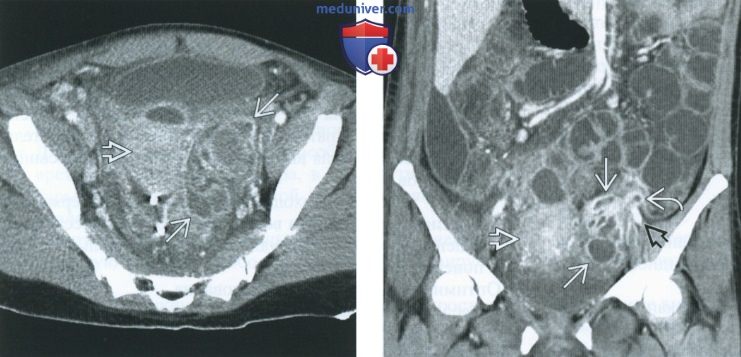

КТ-исследование абсцесса малого таза: Визуализация и диагностика

Раздел: Фотоальбом решений